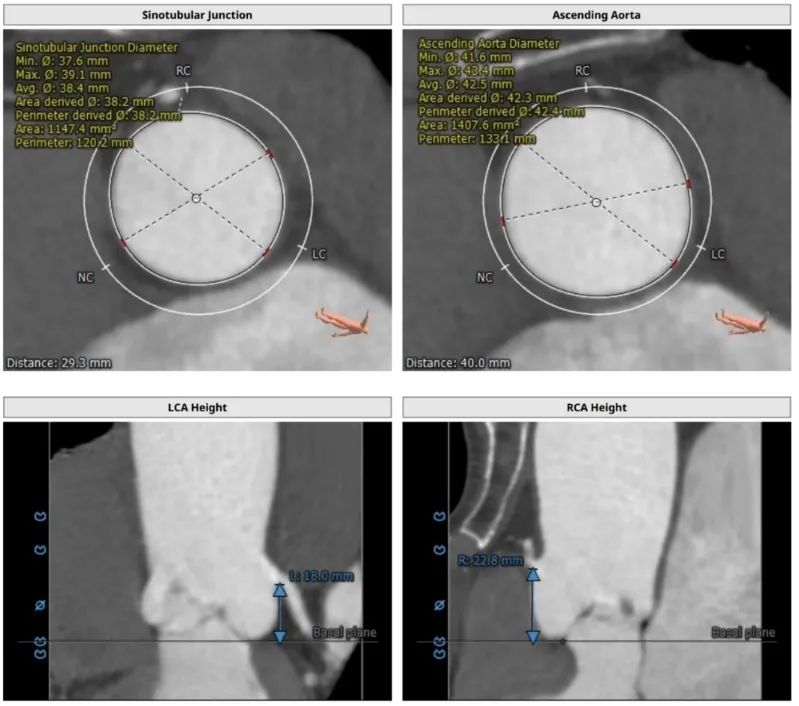

CT评估:三叶式主动脉瓣,瓣叶轻度增厚,无钙化,瓣环85.6mm,窦直径38~42mm。

主动脉瓣根部解剖